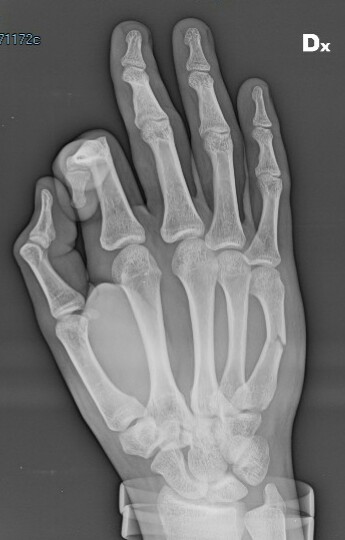

Salve sono un ragazzo di 17 anni che ha subito una forte contusione provocando una frattura composta del V metacarpo della mano dx. Recandomi in pronto soccorso mi hanno fatto un rx e ingessato bloccando mignolo e anulare per 30 giorni.. siccome sono già 8 giorni che porto il gesso ( premetto che mi sono recato in ps dopo 7 giorni, pensando fosse una contusione) la mia domanda è, guardando il tipo di frattura, siccome non sopporto il gesso per il caldo è per i fastidi che provoca.... Posso già toglierlo? La frattura di consoliderà lo stesso? Cosa potrebbe succedere?

Commento file: Rx dopo 7 giorni